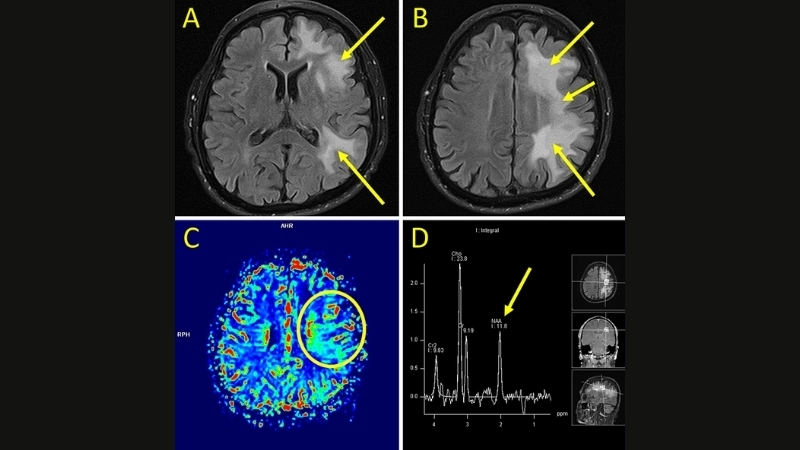

PML diagnosis relies on MRI and JC virus detection